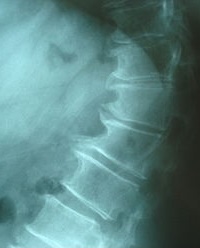

Thoracic Spondylosis.JPG

Thoracic spondylosis

Spondylosis is the degeneration of the vertebral column from any cause. In the more narrow sense it refers to spinal osteoarthritis, the age-related wear and tear of the spinal column, which is the most common cause of spondylosis. The degenerative process in osteoarthritis chiefly affects the vertebral bodies, the neural foramina and the facet joints (facet syndrome). If severe, it may cause pressure on the spinal cord or nerve roots with subsequent sensory or motor disturbances, such as pain, paresthesia, imbalance, and muscle weakness in the limbs.